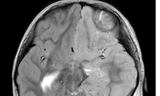

Thay vì loại bỏ một phần não của cô bé như các bác sĩ từng làm, bác sĩ giải phẫu thần kinh nhi khoa, Tiến sĩ Aaron Robison, thuộc Đại học Y tế Loma Linda, cho biết việc tắt một nửa bộ não của cô bé là phương pháp hiệu quả nhất.

Các bác sĩ đã quyết định tắt phần não không hoạt động của cô bé bằng cách can thiệp qua lỗ mở tự nhiên của não được gọi là khe nứt sylvian. Phía bên trái vẫn hoạt động và hiện đang đảm nhận các nhiệm vụ mà phía bên phải từng đảm nhiệm. Các bác sĩ cho biết, cô bé có thể mất một số thị lực ngoại vi và một số kỹ năng vận động tinh ở tay trái, nhưng vật lý trị liệu sẽ giúp bé trở lại là một đứa trẻ 6 tuổi như bình thường.